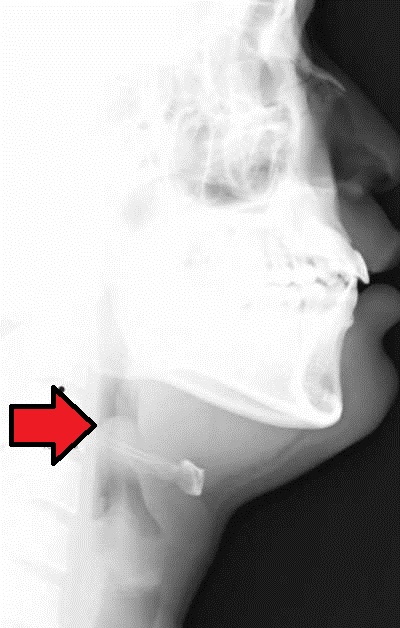

- 경부 측면 X선 사진: 기도와 후두개, 경부 연부 조직의 형태를 평가한다. X선 사진상 비대한 후두개는 "엄지손가락 인상 징후(thumb sign)", 후두개곡의 소실은 "Vallecula sign"이라고 불린다.

후두경을 사용한 직접 검사로 확진할 수 있지만, 기도 경련을 유발할 수 있으므로 주의해야 한다.[19] 이러한 이유로 설압자를 사용하여 후두개를 관찰하는 것은 권장되지 않는다. 따라서 수술실과 같이 통제된 환경에서 간접 섬유 내시경 검사를 통해 진단한다.[19] 감염된 후두개는 부어 있으며 "선홍색"을 띤다.[27]측면 경추 X-ray에서 엄지손가락 인상 징후는 부어오르고 확대된 후두개를 나타낸다.[10] 그러나 정상적인 X-ray는 진단을 배제하지 않는다.[10] 초음파(초음파 검사)가 도움이 될 수 있지만, (2018년 기준) 연구 초기 단계에 있다.[10]

경부 측면 X선 사진은 기도와 후두개, 경부 연부 조직의 형태를 평가하는데 사용되며, X선 사진상에서 비대한 후두개는 "thumb sign"이라고 불린다.[49] 후두개곡의 소실(Vallecula sign)도 관찰할 수 있다.[50] 크루프와의 감별을 위해 경부 정면 X선 사진도 참고가 된다.